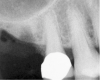

The 2-mm twist drill is used to create an osteotomy 1 mm short of the subantral floor. If any resistance is detected prior to reaching the 3-mm depth, drill penetration must be stopped, because the subantral cortical bone has possibly been reached. Any uncontrolled "push" would penetrate the bone and likely perforate the sinus membrane. A guide pin is then inserted and a radiograph taken to determine if drill penetration has terminated within 1 mm of the subantral floor (Figure 2). If the radiograph indicates that more than 1 mm of bone is present subantrally, the twist drill is used again to penetrate within 1 mm of the sinus floor. Alternately, an osteotomy tip for a piezosurgery unit can be used for this purpose. The final depth of penetration should be verified with another periapical film.

Figure 2  After drilling to a depth of 3 mm with a 2.1-mm twist drill, the guide pin was placed and a radiograph was taken to ascertain if the drill stopped within 1 mm of the subantral floor.

Figure 2